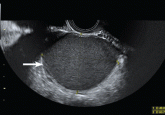

ArticleRole of imaging in endometriosisAuthor:Giuseppe Lo Monte, MDPublish date: June 1, 2014Transvaginal ultrasonography and magnetic resonance imaging confirm the diagnosis and guide surgical treatment.Read More